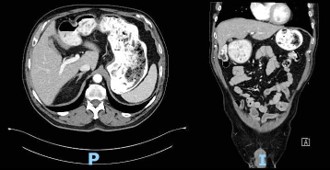

The patient followed an excellent clinical course, with full resolution of the symptoms after three months of treatment. The follow-up CT scan obtained three months (Figure 3) and six months (Figure 4) after admission revealed the complete dissolution of the bezoar. Annual clinical follow-up was performed until June 2025, with no recurrence of symptoms of bezoar reformation.

Figure 3: Computed tomography scan at three-month follow-up.